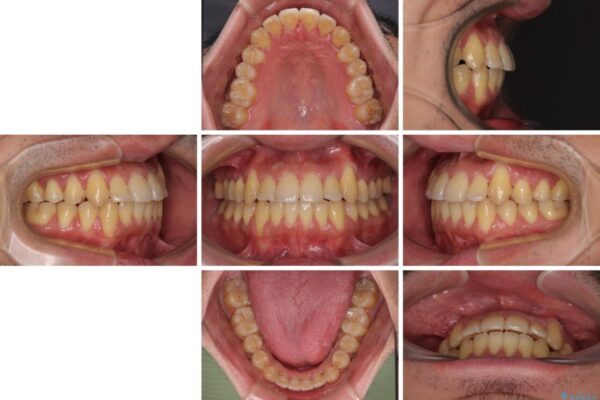

八重歯と前歯のクロスバイトを改善したいとのことで来院された患者様です。

デコボコの程度は強かったのですが、口元の突出感はなかったため、非抜歯矯正としました。

治療前

• 八重歯とクロスバイト 目立たないワイヤー装置で矯正治療 治療前画像